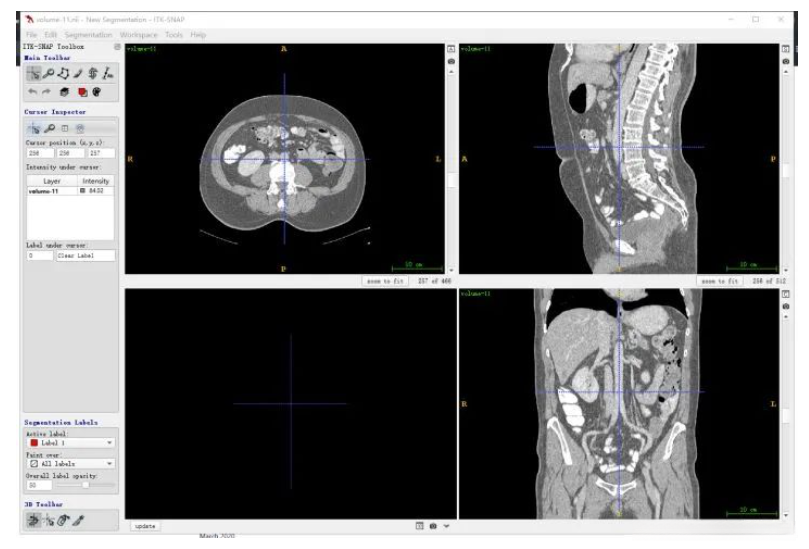

首先要明确一下和人体对应的方向,其中三个窗口对应三个切面,对应关系如下图所示,按照字母索引即可。例如,左上图对应R-A-L-P这个面,是从脚底往头部方向看的切面(即z方向),另外两张类似。

红色切面为矢状面,紫色切面为冠状面,绿色切面为横断面